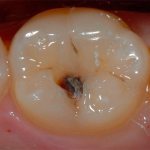

- поверхностный кариес – кариозная полость в пределах эмали;

- средний кариес – кариозная полость в пределах эмали и поверхностных слоях дентина;

- фиссурный: в зубных бороздках (фиссурах или углублениях) на премолярах и молярах.

Хронический средний кариес можно заметить сразу, так как на эмали виднеется отверстие, имеющее твёрдые стенки. Кариес протекает длительное время, и не подаёт совершенно никаких симптомов. В этом и заключается его опасность, так как промежуточная стадия может плавно перейти в глубокий кариес. Патологический процесс локализуется преимущественно на жевательной поверхности зубов.

Для острого среднего кариеса также характерно образование полости, но её края очень хрупкие и она заполнена размягчённым дентином. Такой патологический процесс локализуется в области шейки зуба, а также в фиссурах.